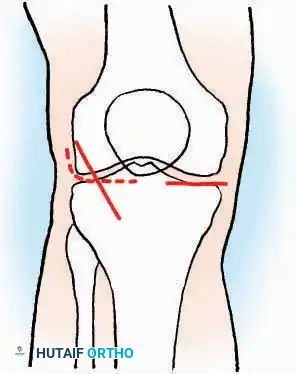

SURGICAL APPROACHES TO THE TOES

Pathologies of the forefoot, including hallux valgus, rigidus, and lesser toe deformities (hammer, claw, and mallet toes), require precise surgical exposures that respect the delicate dorsal and plantar neurovascular bundles.

Approaches to the Interphalangeal (IP) Joints

The neurovascular bundles of the toes run in the plantar-medial and plantar-lateral quadrants. Dorsal incisions or midaxial incisions are preferred to avoid painful plantar scars and iatrogenic nerve injury.

Indications: Arthrodesis for hammer toe deformities, excision of intra-articular osteophytes, or reduction of irreducible dislocations.

Surgical Technique:

* Great Toe: Make a 2.5 cm longitudinal incision strictly on the medial midaxial aspect of the toe.

* Fifth Toe: Utilize a lateral midaxial incision to avoid interdigital maceration.

* Lesser Toes (2nd, 3rd, 4th): Approach the IP joints through a dorsal longitudinal incision placed just lateral to the corresponding extensor digitorum longus (EDL) tendon.

* Deep Dissection: Carry the dissection sharply through the subcutaneous tissue and superficial fascia directly to the joint capsule.

* Neurovascular Protection: Reflect the skin edges with meticulous care. Retract the dorsal digital nerves and vessels dorsally, and the plantar nerves and vessels plantarward.

* Capsulotomy: Open the capsule either transversely (for joint resection/arthrodesis) or longitudinally (for exploration), exposing the articular surfaces.